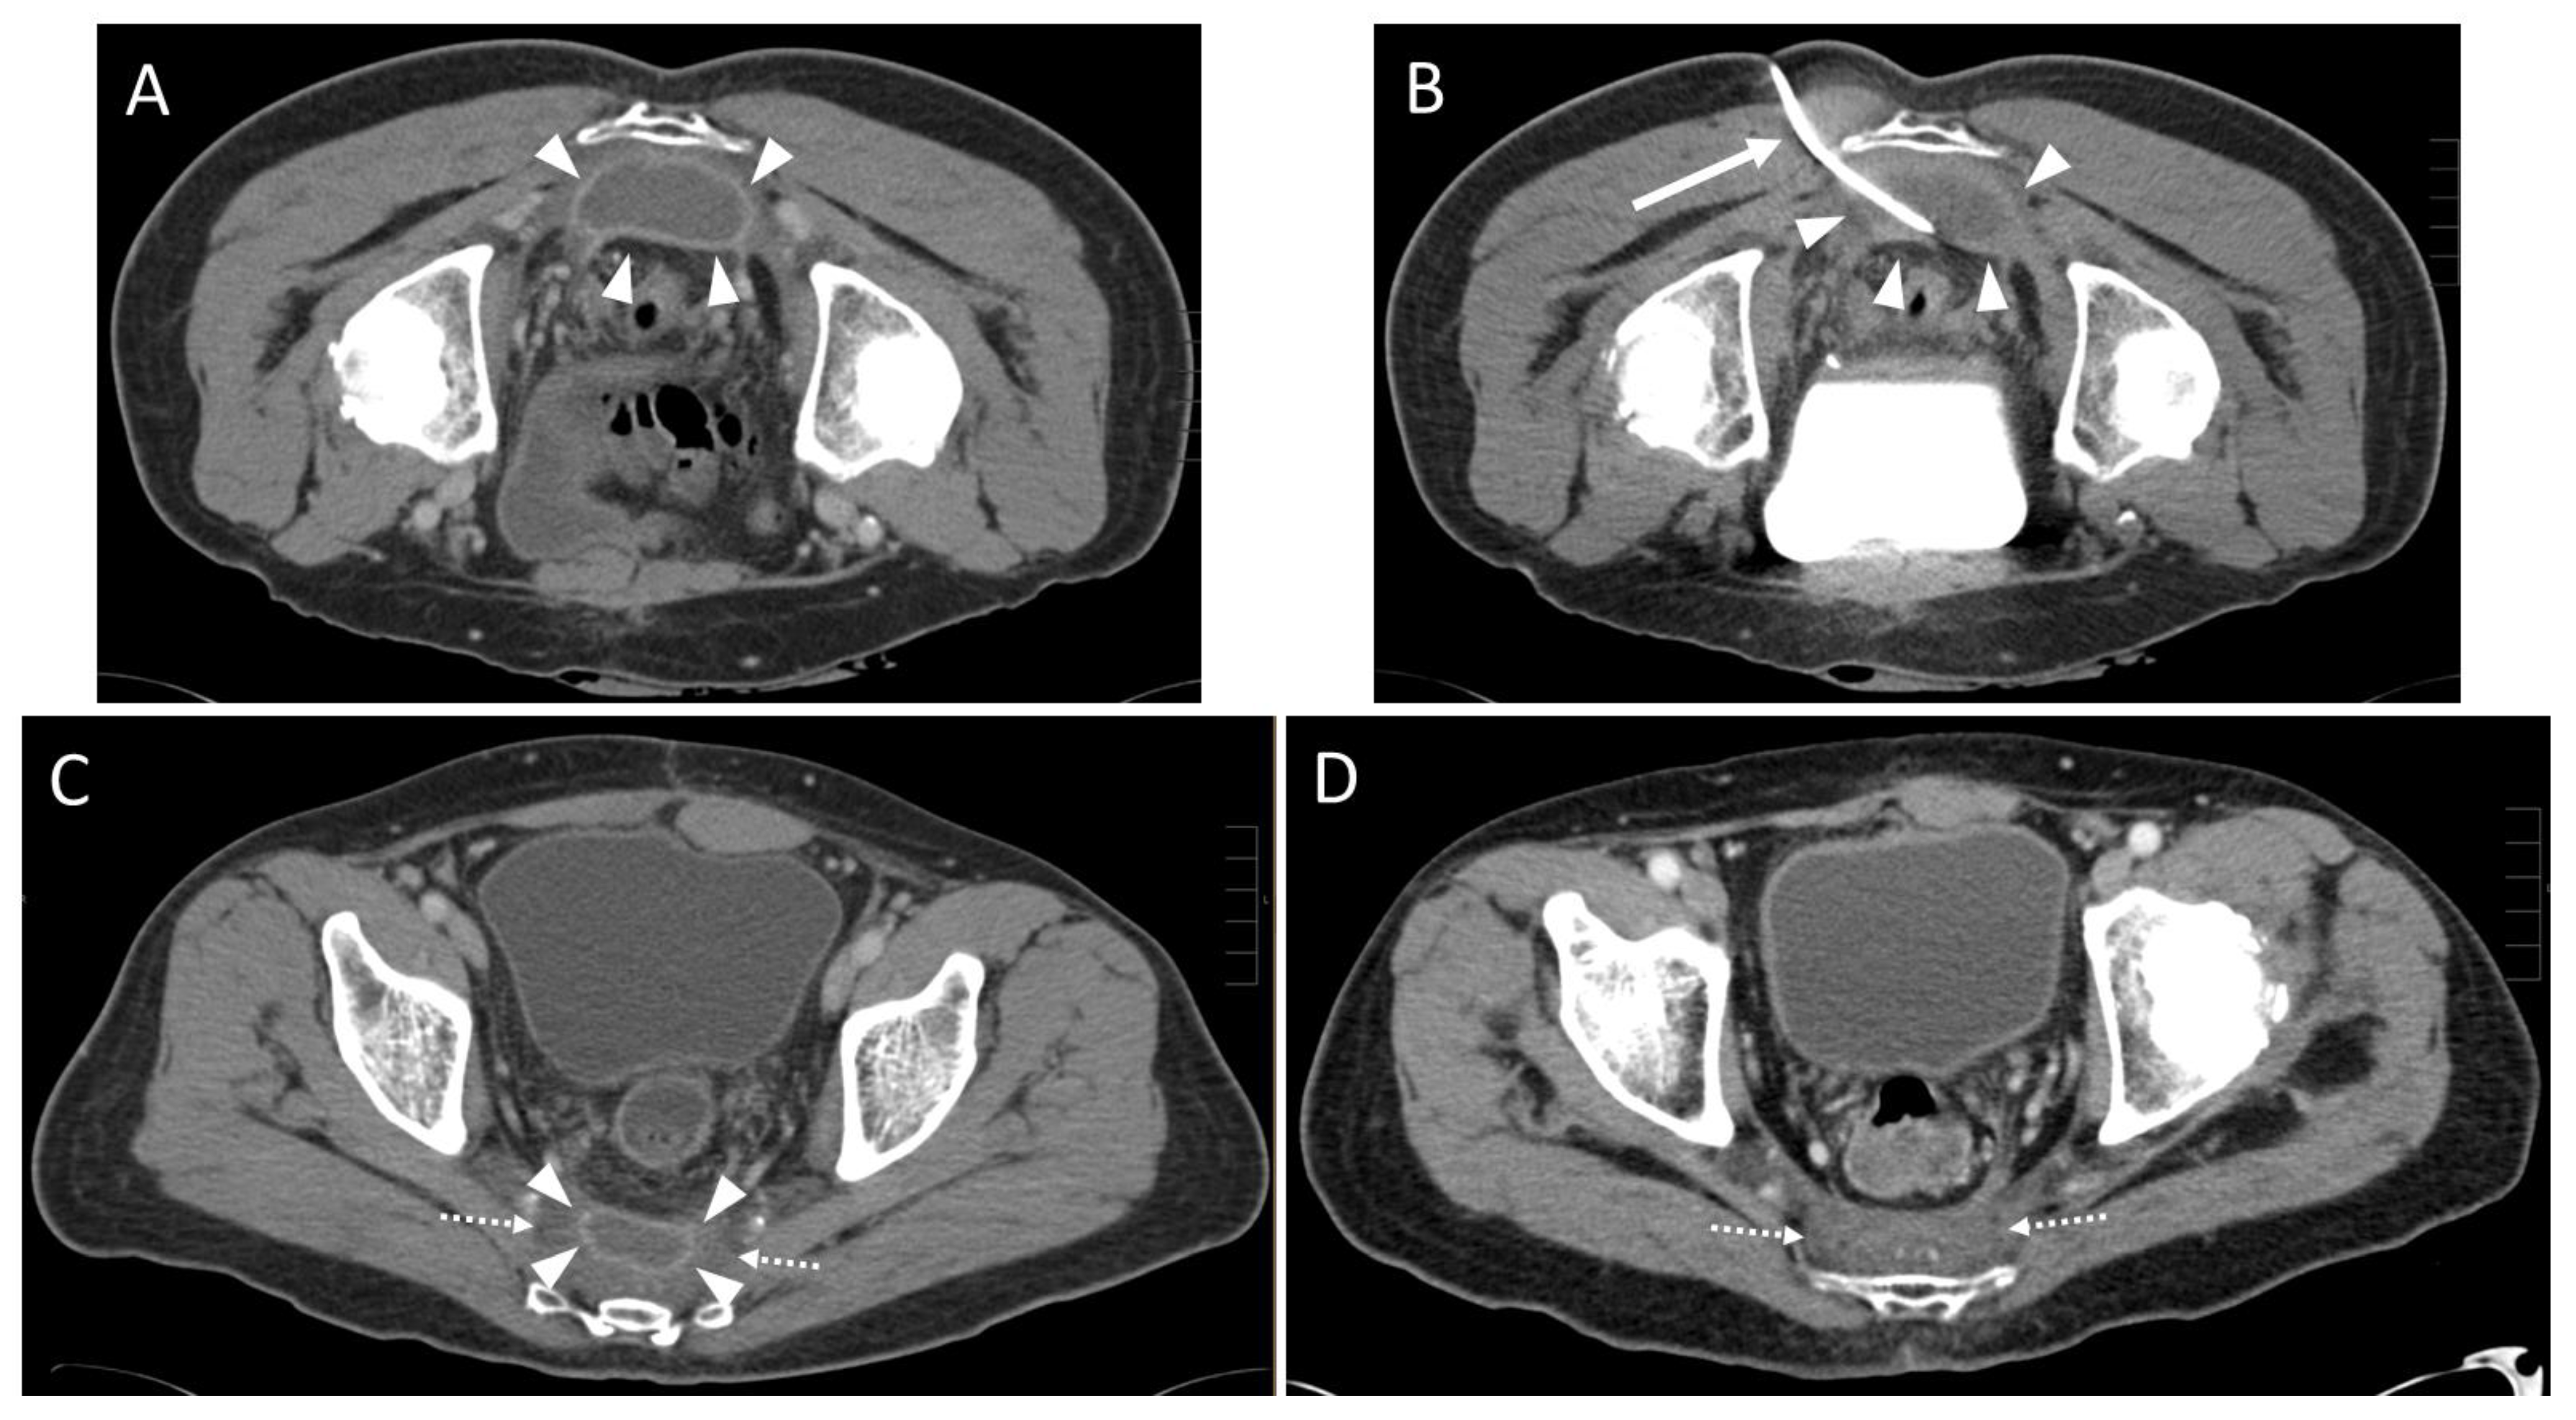

| Approach | |

| parasacral | 29 (72.5%) 3 |

| paracoccygeal | 10 (25.0%) 3 |

| infracoccygeal | 1 (2.5%) 3 |

| Access path | Count |

| transpiriform | 8 (20.0%) 3 |

| infrapiriform | 31 (77.5%) 3 |

| transperineal | 1 (2.5%) 3 |